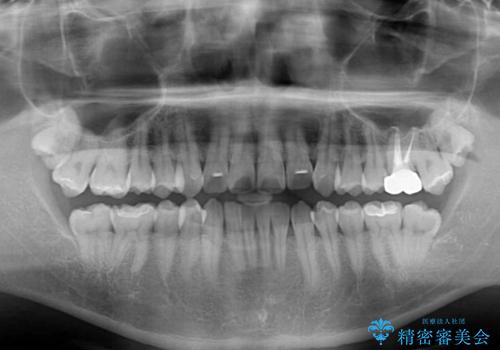

- 前歯のデコボコを治したいとのことで来院された患者様です。

上下顎ともに歯列全体の後方移動とIPR(歯と歯の間を削る)によってデコボコが解消するように設計し、インビザラインにより治療を行うこととしました。

毎日22時間以上しっかりとマウスピースを装着していただいたので、スムーズに治療が進みました。歯と歯の間を削ることでうまくスペースコントロールでき、1年強で終えることができました。